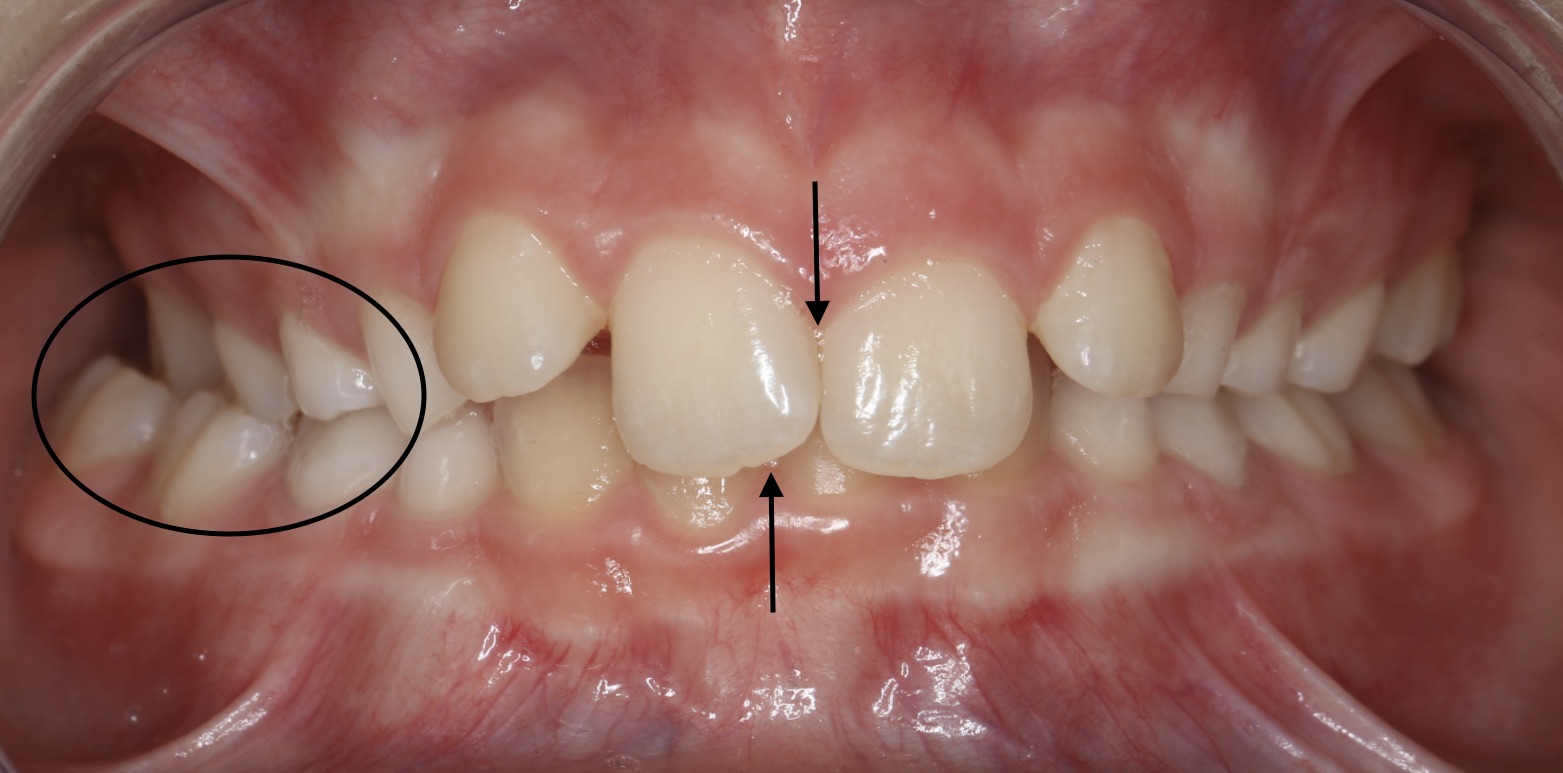

Hier laten wij een voorbeeld zien. Meisje van 10 jaar met een smalle bovenkaak. Hierdoor past de onderkaak er niet goed tussen en bijt ze aan de rechterkant (voor de kijkers links) in een kruisbeet.

De middens van boven- en ondertandboog zijn niet gelijk, omdat ze naar rechts in kruisbeet dichtbijt nu de onderkaak niet recht in de bovenkaak past.